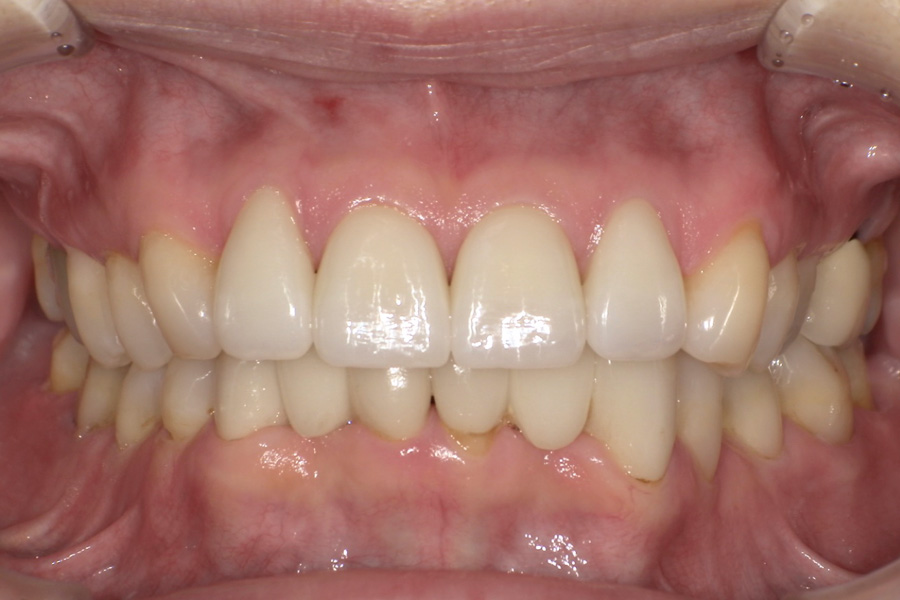

虫歯があるから削ったり悪くなったから抜くのではなく、まずは虫歯と歯周病が起きないようにより良い環境づくりをすること、そうすることによって歯を長く維持することが可能となります。

そのためには、健康状態に関する情報と生活習慣などの状況を把握したうえで、お口の中のリスク評価をおこないます。

その結果をもとに、お一人お一人にあった治療計画をご提案させていただきます。